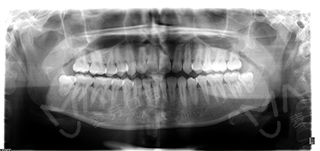

对华小雪的牙齿仔细检查后,并通过科学的德国卡瓦数字化口腔CT三维检测,张超主任指出做金属的托槽矫正需要拔牙,而且还影响形象,最终华小雪量身定制矫牙方案——隐适美隐形矫正。经过口内取模,3d效果演示预测矫正后的牙齿形态,华小雪终于戴上了属于自己的牙套。